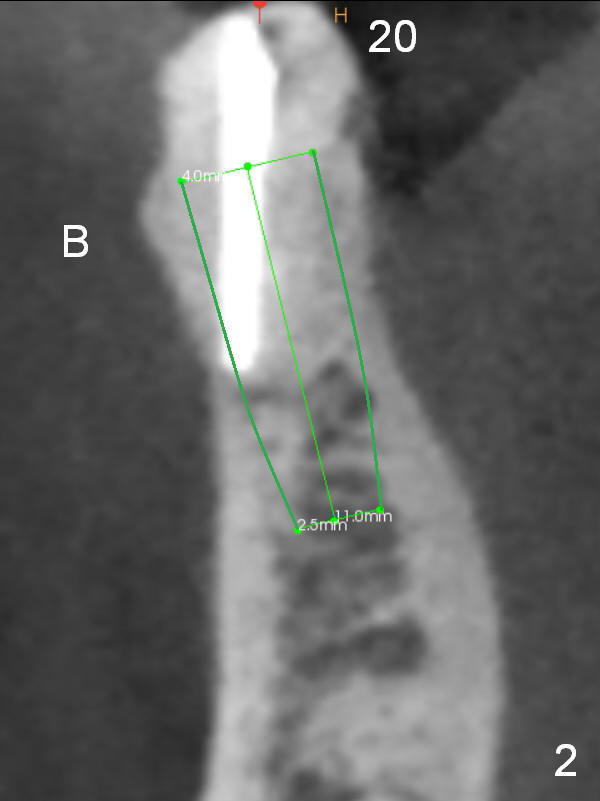

A 71-year-old man requests restoration at #18-20 (Fig.1). Placing implants at the narrow ridge of the sites of #18 and 19 is quite challenging (Fig.3,4), as compared that at #31 (Fig.5). Since the bone density at the crest is high (1200-1500 u), use a surgical high speed fissure bur for sectioning the crest, followed by BEB at 11 mm. It appears safer to place 1-piece implant (Fig.3) than 2-piece one (Fig.4). Since the total mesiodistal distance for #18-20 is 18 mm, splinting the three-units should be a sound treatment option.

After removing the residual root at #20, no antibiotic will be used for socket disinfection except gauze. It seems that an implant smaller than 4 mm is needed (Fig.1,2).